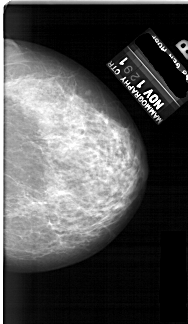

A_1691_1.LEFT_CC

LEFT_CC LINES 6871 PIXELS_PER_LINE 3946 BITS_PER_PIXEL 12 RESOLUTION 43.5 OVERLAY